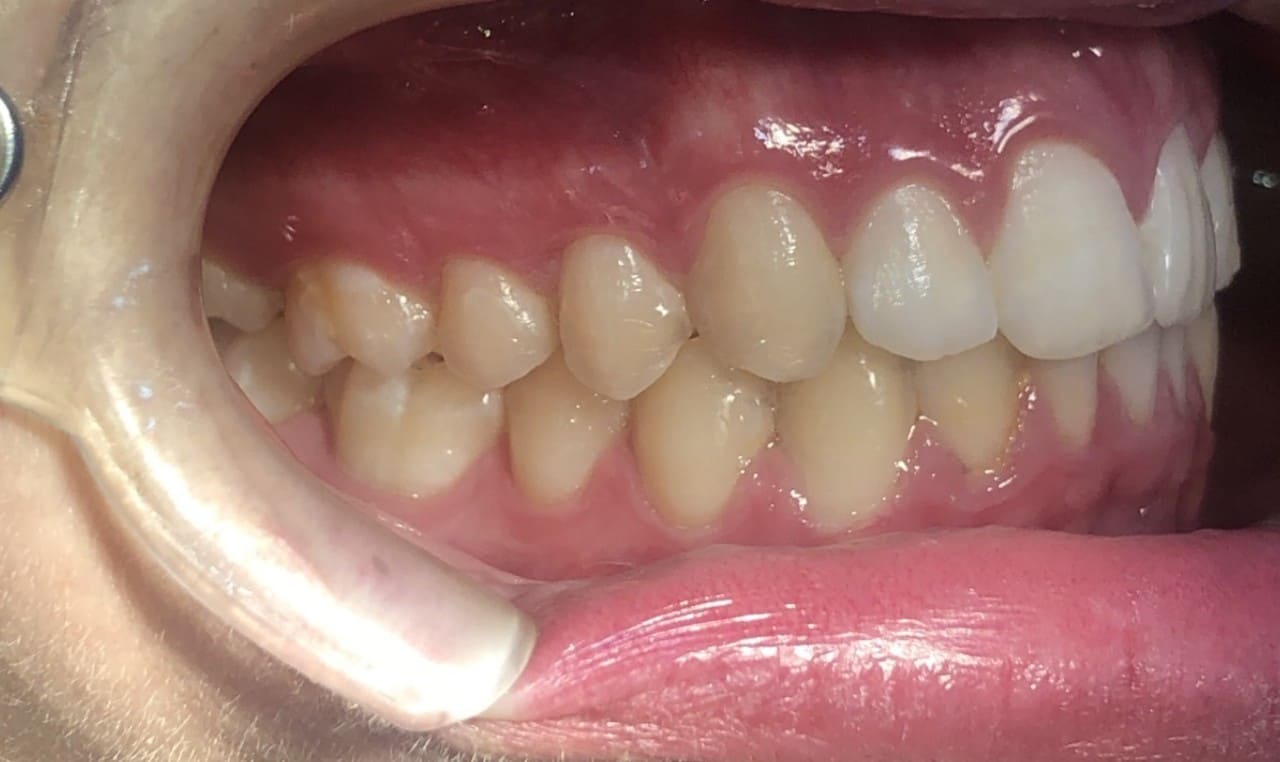

Invisalign Teen Conditions – Class II div 1 – Deep bite – Increased overjet – Narrow arches

Clinical Indications

- Class II div 1

- Deep bite

- Increased overjet

- Narrow arches

Initial